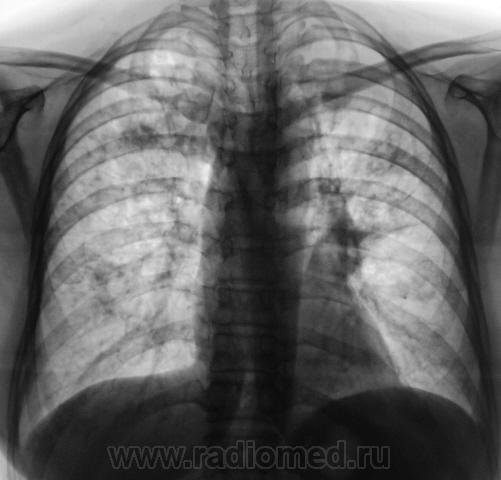

2009 г.

Нужно дифференцировать, исход диссеменированного туберкулёза ( в 2008г.) в множественные туберкулёмы в 2010г, и MTS в лёгкие с некоторой положительной димамикой, возможно на фоне проведённой химеотерапии (нужен анамнез!).

"Палка" была обнаружена, и в 2008 и 2009 гг неоднократно.

Возможно вы правы, но может быть просто, проявлением лечённого диссеминированного туберкулёза лёгких в динамике.